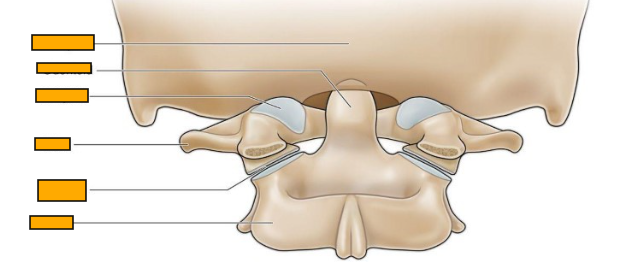

Label from top to bottom

occiput (back of the head)

odontoid

AO joint

atlas

AA joint

axis

Where does C1/atlas articulate

-articulates with the base of the skull (occiput) via the atlanto-occipital joint (nodding/ up and down movement)

-articulates with axis/C2 via the atlanto-axial joint for side-to-side rotation)

atlanto-occipital joint

atlanto-axial joint

What type of joints are AO joints

condyloid joints (type of synovial joint)

Features of AO joints

classified as synovial joints with capsules

very mobile with primarily ligamentous stabilisation

facilitate occipital flexion and extension on the atlas/C1

What type of joints are the AA joint

pivot joint

How many AA joints are there

3

What type of movement do the AA joints allow and how

rotation / side to side movement of the head

there is a pivot joint between the odontoid process of the axis and ring formed by the anterior arch and the transverse ligament of the atlas